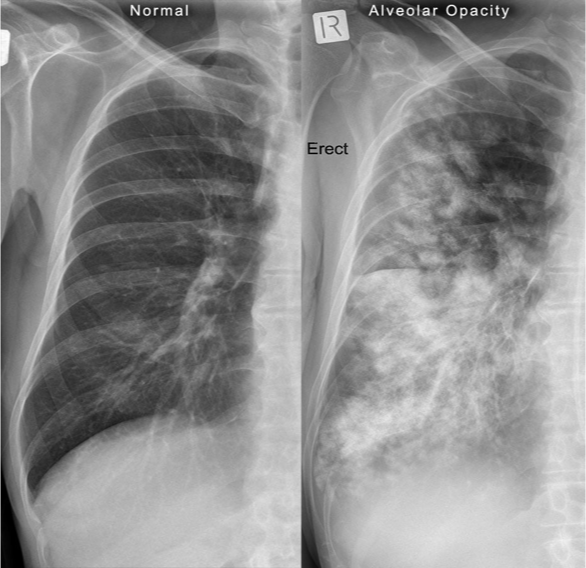

Radiographic finding described as poorly marginated density or “fluffy”

alveolar infilatrate

NOTE: alveolar infiltrates can appear as fluffy or as complete consolidations

Pattern seen on CXR or CT scans when air-filled bronchi become visible against a background of dense lung tissue.

Air bronchogram sign